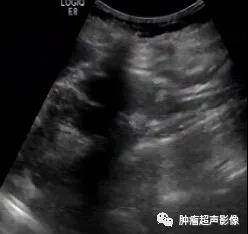

超声检查发现双肾多发AML,尤其是肿瘤数目较多、瘤体较大、肾脏轮廓不清时要想到TSC的可能,并询问相关病史,并观察面部、建议颅脑CT检查等。肾囊肿在TSC中也较常见,是该病临床诊断的次要指征。肝AML在超声上与血管瘤表现类似,均表现为大小不等圆形或椭圆形偏强回声团块,肝AML含有脂肪成分,回声比血管瘤回声更强一些,结合TSC病史,肝脏多发偏强回声占位应首先考虑为AML。

体检发现双肾多发错构瘤,双肾密集分布,考虑结节性硬化症表现,建议头颅检查(病例由江口县人民医院胡海英医师提供)

女,61,因肾肿瘤入院治疗,超声及CT示两肾多发错构瘤,建议头颅检查。